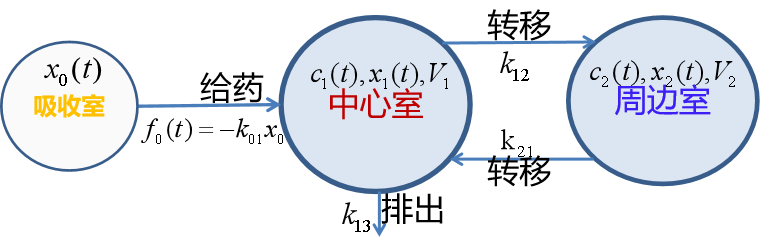

下面只考虑房室之间、房室与体外转移速率为常数的二房室模型(乳突状模型),如图13所示。

图13 二房室模型

3、口服或肌肉注射

这种给药方式相当于在药物进入中心室以前,先有个将药物吸收入血液的过程,可以简化为一个吸收室,如图15所示,x0(t)是吸收室的药量,药物由吸收室进入中心室的速率为k01。

图15 详细的三房室模型